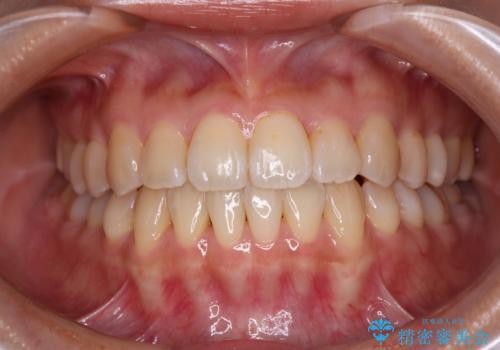

- 上下前歯のデコボコと、それによる磨きづらさを気にして来院された患者様です。

叢生解消のため、上下左右第一小臼歯4本を抜歯し、ワイヤー装置にて矯正治療を行うこととしました。

半年ほどで前歯のデコボコは改善され、汚れの溜まりやすさは解消されました。

抜歯スペースを閉じるために期間がかかりましたが、当初予定通り2年強で終えることができました。